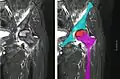

Radiography of avascular necrosis of left femoral head. Man of 45 years with AIDS.

Nuclear magnetic resonance of avascular necrosis of left femoral head. Man of 45 years with AIDS.